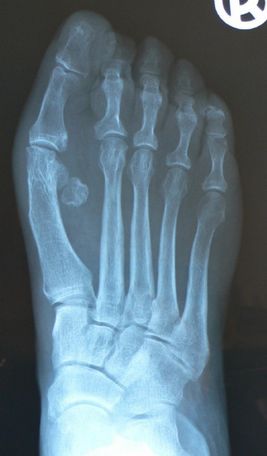

Left: X-ray before surgery

Right: X-ray after correction of the hallux with the 30mm plate and correction of the rigid hammer toes II and III with micro screws